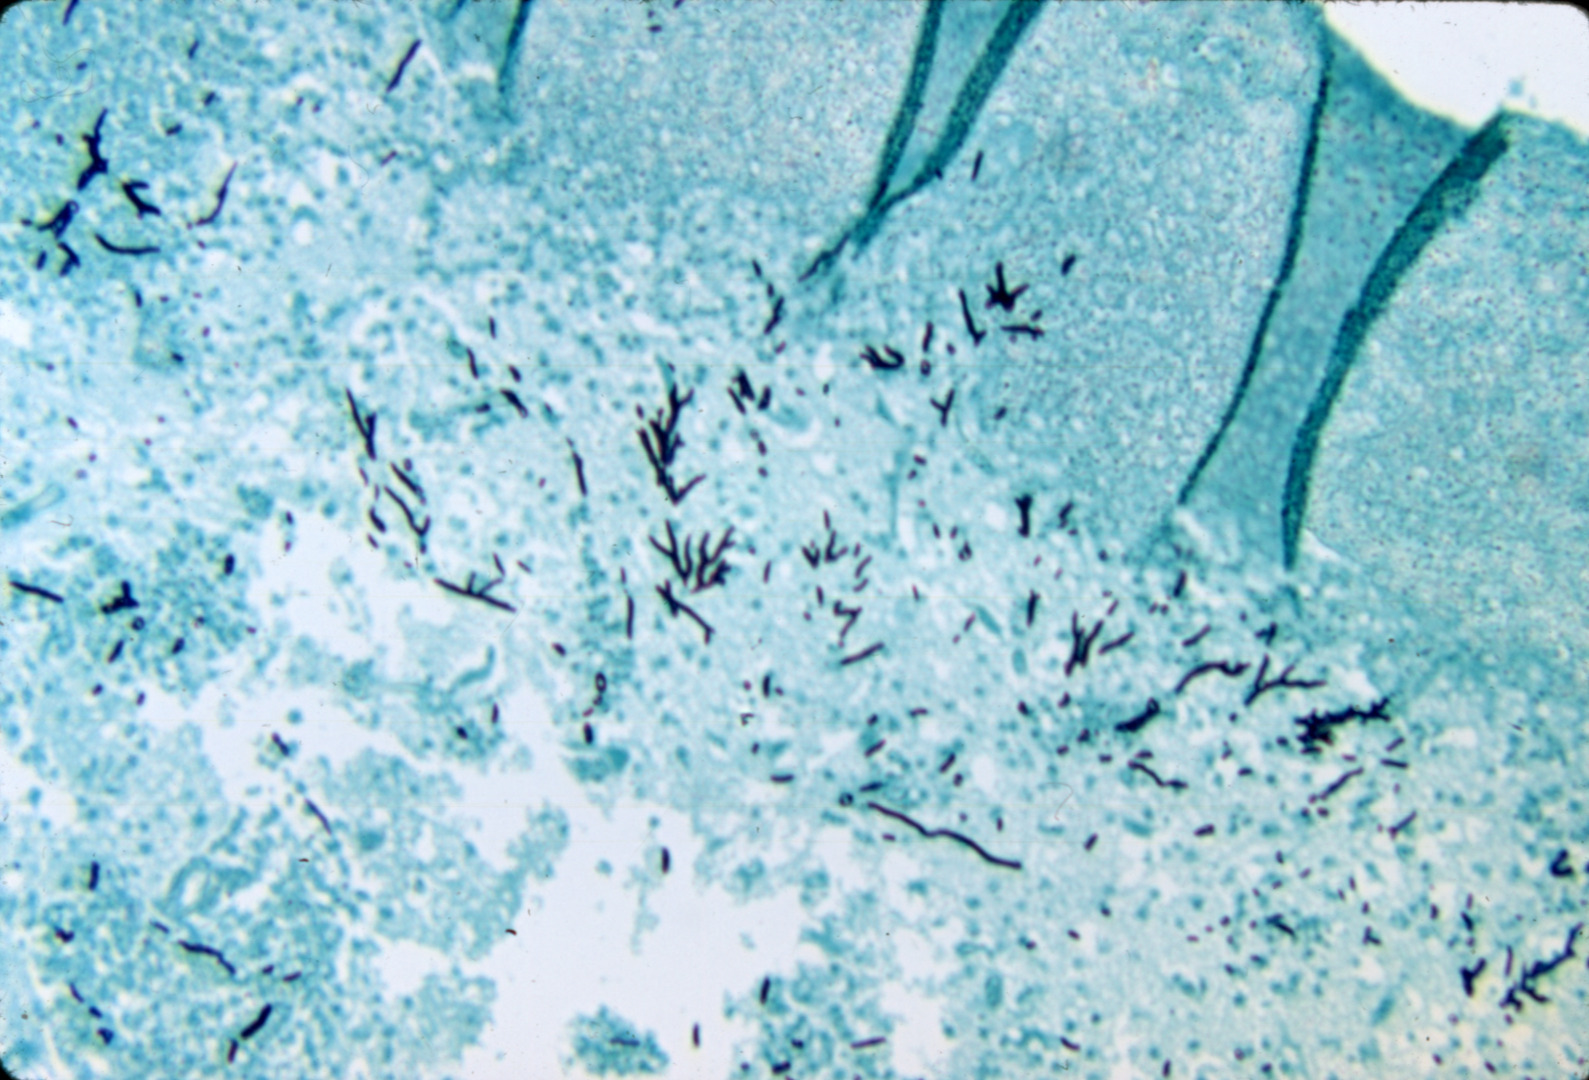

Aspergillosis-dactylariosis (slide study set no. 9)

Poultry--Diseases Aspergillosis

Slide Study Set #9, Aspergillosis-Dactylariosis (includes 24 color slides), 1978